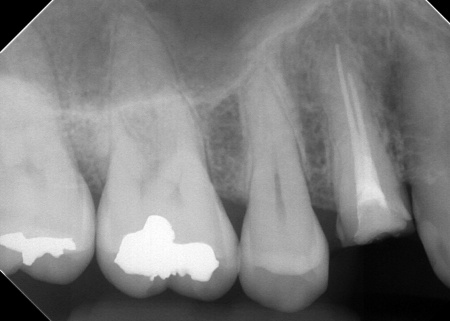

また右上奥歯には、歯根の先に炎症が起きて膿が溜まる根尖性(こんせんせい)歯周炎が認められます。

②根尖性歯周炎を発症している右上奥歯には、歯根内の細菌を除去して薬を詰める「根管治療」を実施し、歯の温存を図ります。患者様は、以前同じ歯に根管治療を行った経験があったため「再根管治療」となります。

次に、右上奥歯の古い材料(以前の根管治療に使用したもの)を除去し、歯根内部の洗浄と消毒をしてから新しい材料で密封し、被せ物を作製して装着しました。